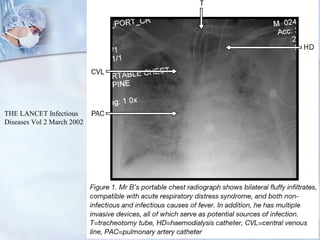

Causas infecciosas Causa + común de infecciones: NAV, IVU, sinusitis, ISO, bacteremia 2ria a colonización de catéter  Neumonía Incidencia y mortalidad alta, prolonga estadía  Se sospecha un exceso de uso de AB por sospecha de NAV Estudio comparativo entre tto x 3 días Vs tto estándar Tto corto: < estancia, costos, resistencia, sin efectos adversos o mortalidad. Deberían los ptes con infiltrados en Rx y baja probabilidad para neumonía recibir tto? THE LANCET Infectious Diseases Vol 2 March 2002

Causas infecciosas Causa+ común de infecciones: NAV, IVU, sinusitis, ISO, bacteremia 2ria a colonización de catéter Neumonía Incidencia y mortalidad alta, prolonga estadía Se sospecha un exceso de uso de AB por sospecha de NAV Estudio comparativo entre tto x 3 días Vs tto estándar Tto corto: < estancia, costos, resistencia, sin efectos adversos o mortalidad. Deberían los ptes con infiltrados en Rx y baja probabilidad para neumonía recibir tto? THE LANCET Infectious Diseases Vol 2 March 2002